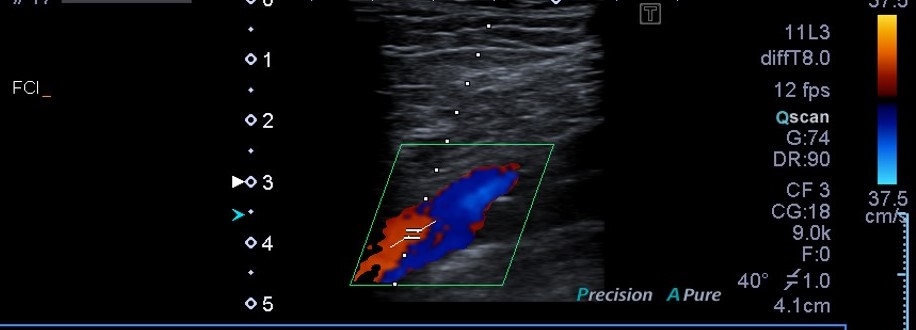

Ecografía venosa Doppler de MID: No signos de TVP aguda.

Dada la falta de respuesta a la antibioterapia, se realizó una ecografía descartándose TVP. Ante la posibilidad de que el cuadro se tratara de un brote de artritis, se solicitaron cifras de ácido úrico que fueron normales, se realizó estudio de radiografía simple de rodillas y muñecas donde se evidenciaron datos de condrocalcinosis, haciendo probable el diagnóstico de enfermedad por depósito de pirofosfatos.